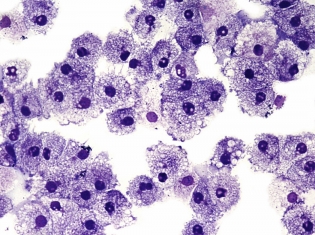

Naegleria fowleri is the name of a free-living amoeba that has claimed three lives this summer - two kids and one man. People are advised not to jump or swim in any warm, stagnant bodies of water.

N. fowleri is the only species of its kind that infects people. The parasite enters through the nose of individuals and makes its way to the brain. Once in the brain, it destroys tissue in the brain which causes sudden headaches, fever, vomiting, stiff neck, lethargy (feeling lazy/sluggish), and coma.